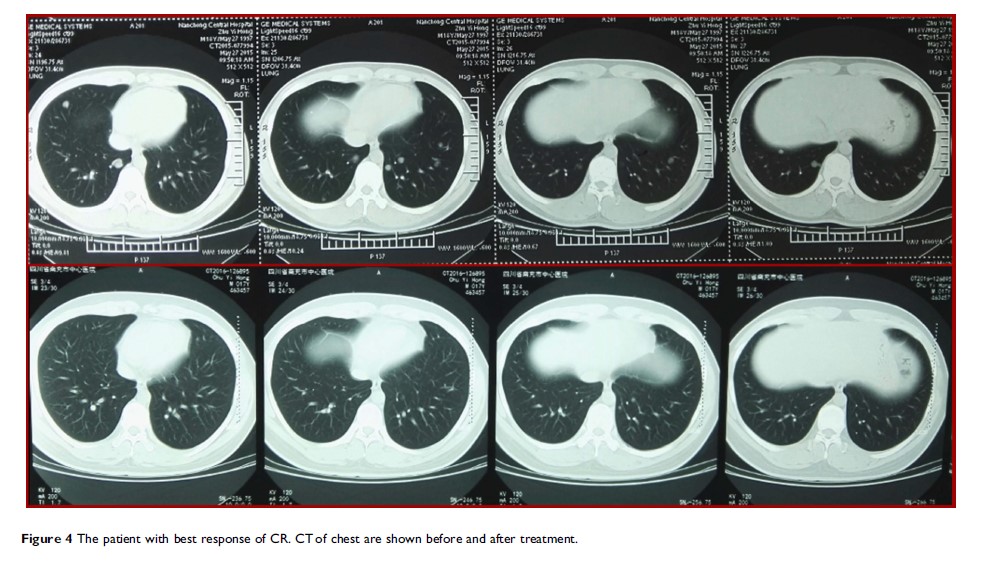

- 作者:Chengzhi Huang, Jianhua Liu, Lishu Xu, Weixian Hu, Junjiang Wang, Muqing Wang, Xueqing Yao